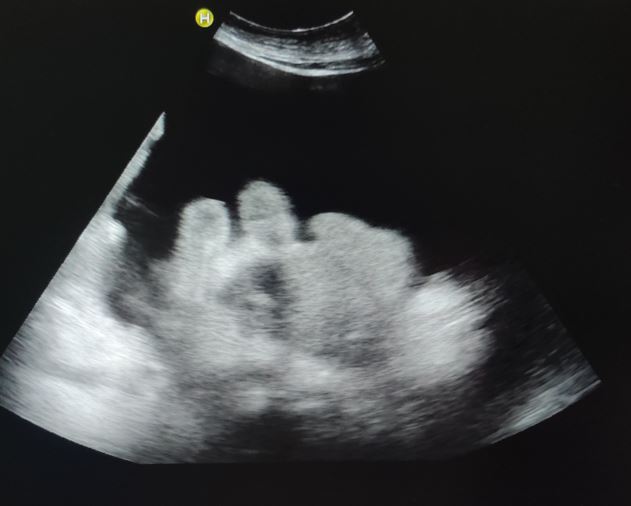

Pruebas complementarias: Analítica: Hb 13 g/dL sin leucocitosis, fibrinógeno 599 mg/dL, TP 20,3s, TTP 31s, gasometría arterial normal, Bb 1,5 mg/dL a expensas de directa 0,7 mg/dL, AST 57 UI/L, GGT 13 UI/l, LDH 152 UI/L, PCR 5 mg/dL. Rx de Tórax y Rx de Abdomen normales. ECG: RS con HBAI con extrasístoles auriculares. Ecografía a pie de cama: abundante líquido libre en cavidad peritoneal y correderas parietocólicas.

Se realiza ecografía para proceder con la paracentesis evacuadora de forma segura, obteniéndose 4200 cc de líquido ascítico claro y se pautan 3 ampollas de albúmina 20%.